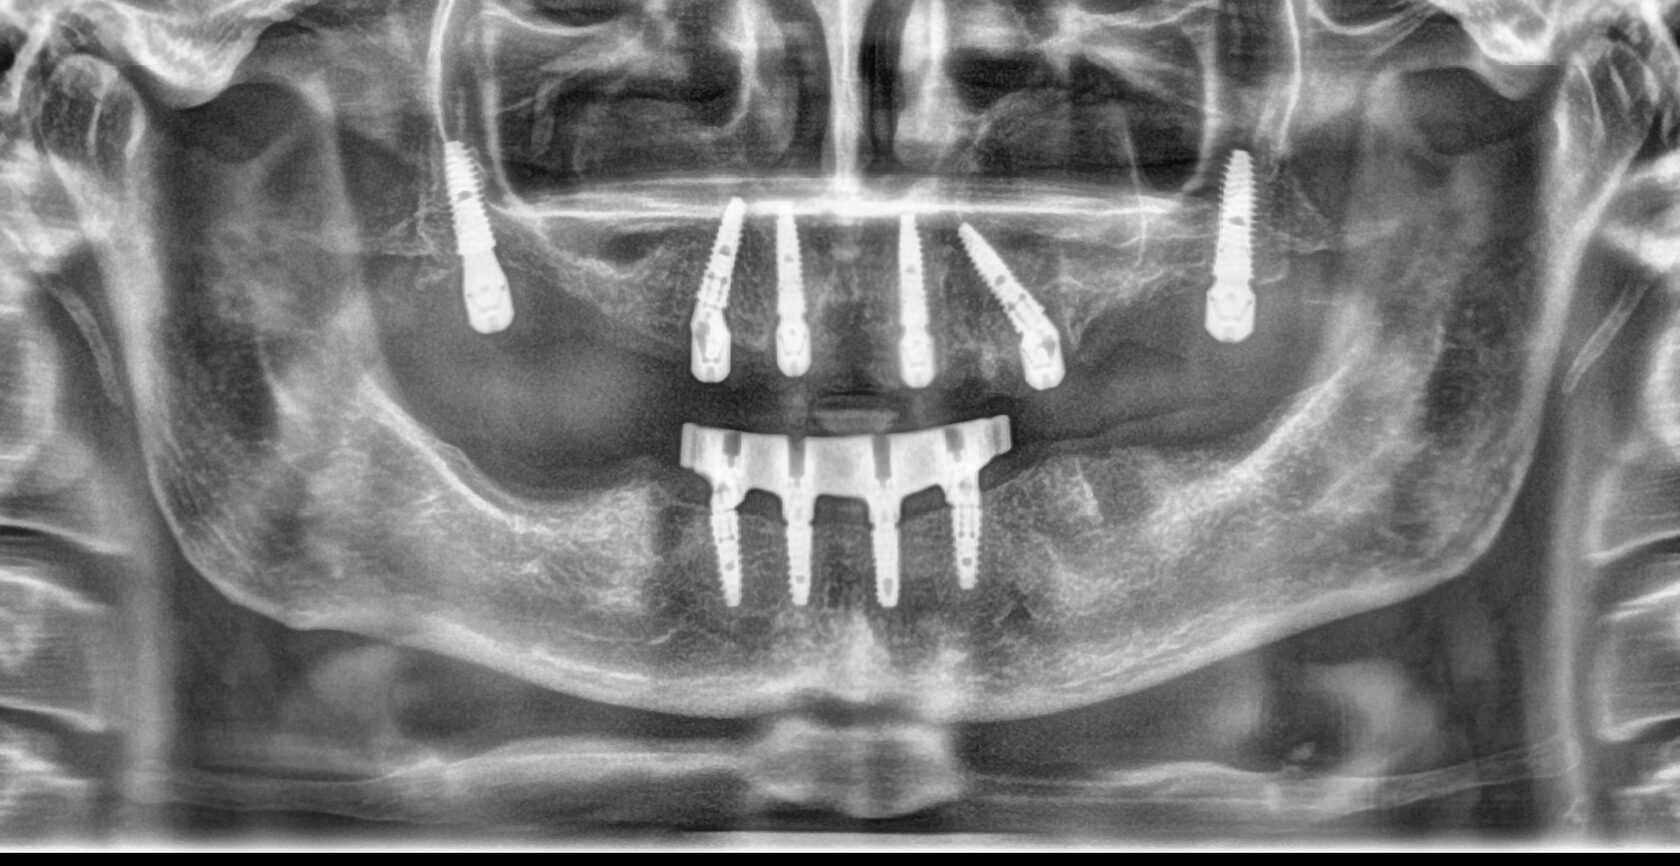

Пример комплексной реабилитации пациента конструкциями с опорой на дентальные

имплантаты при полной адентии.